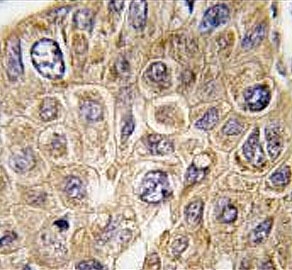

IHC testing of FFPE human hepatocellular carcinoma tissue with Squalene synthase antibody. HIER: steam section in pH6 citrate buffer for 20 min and allow to cool prior to staining.